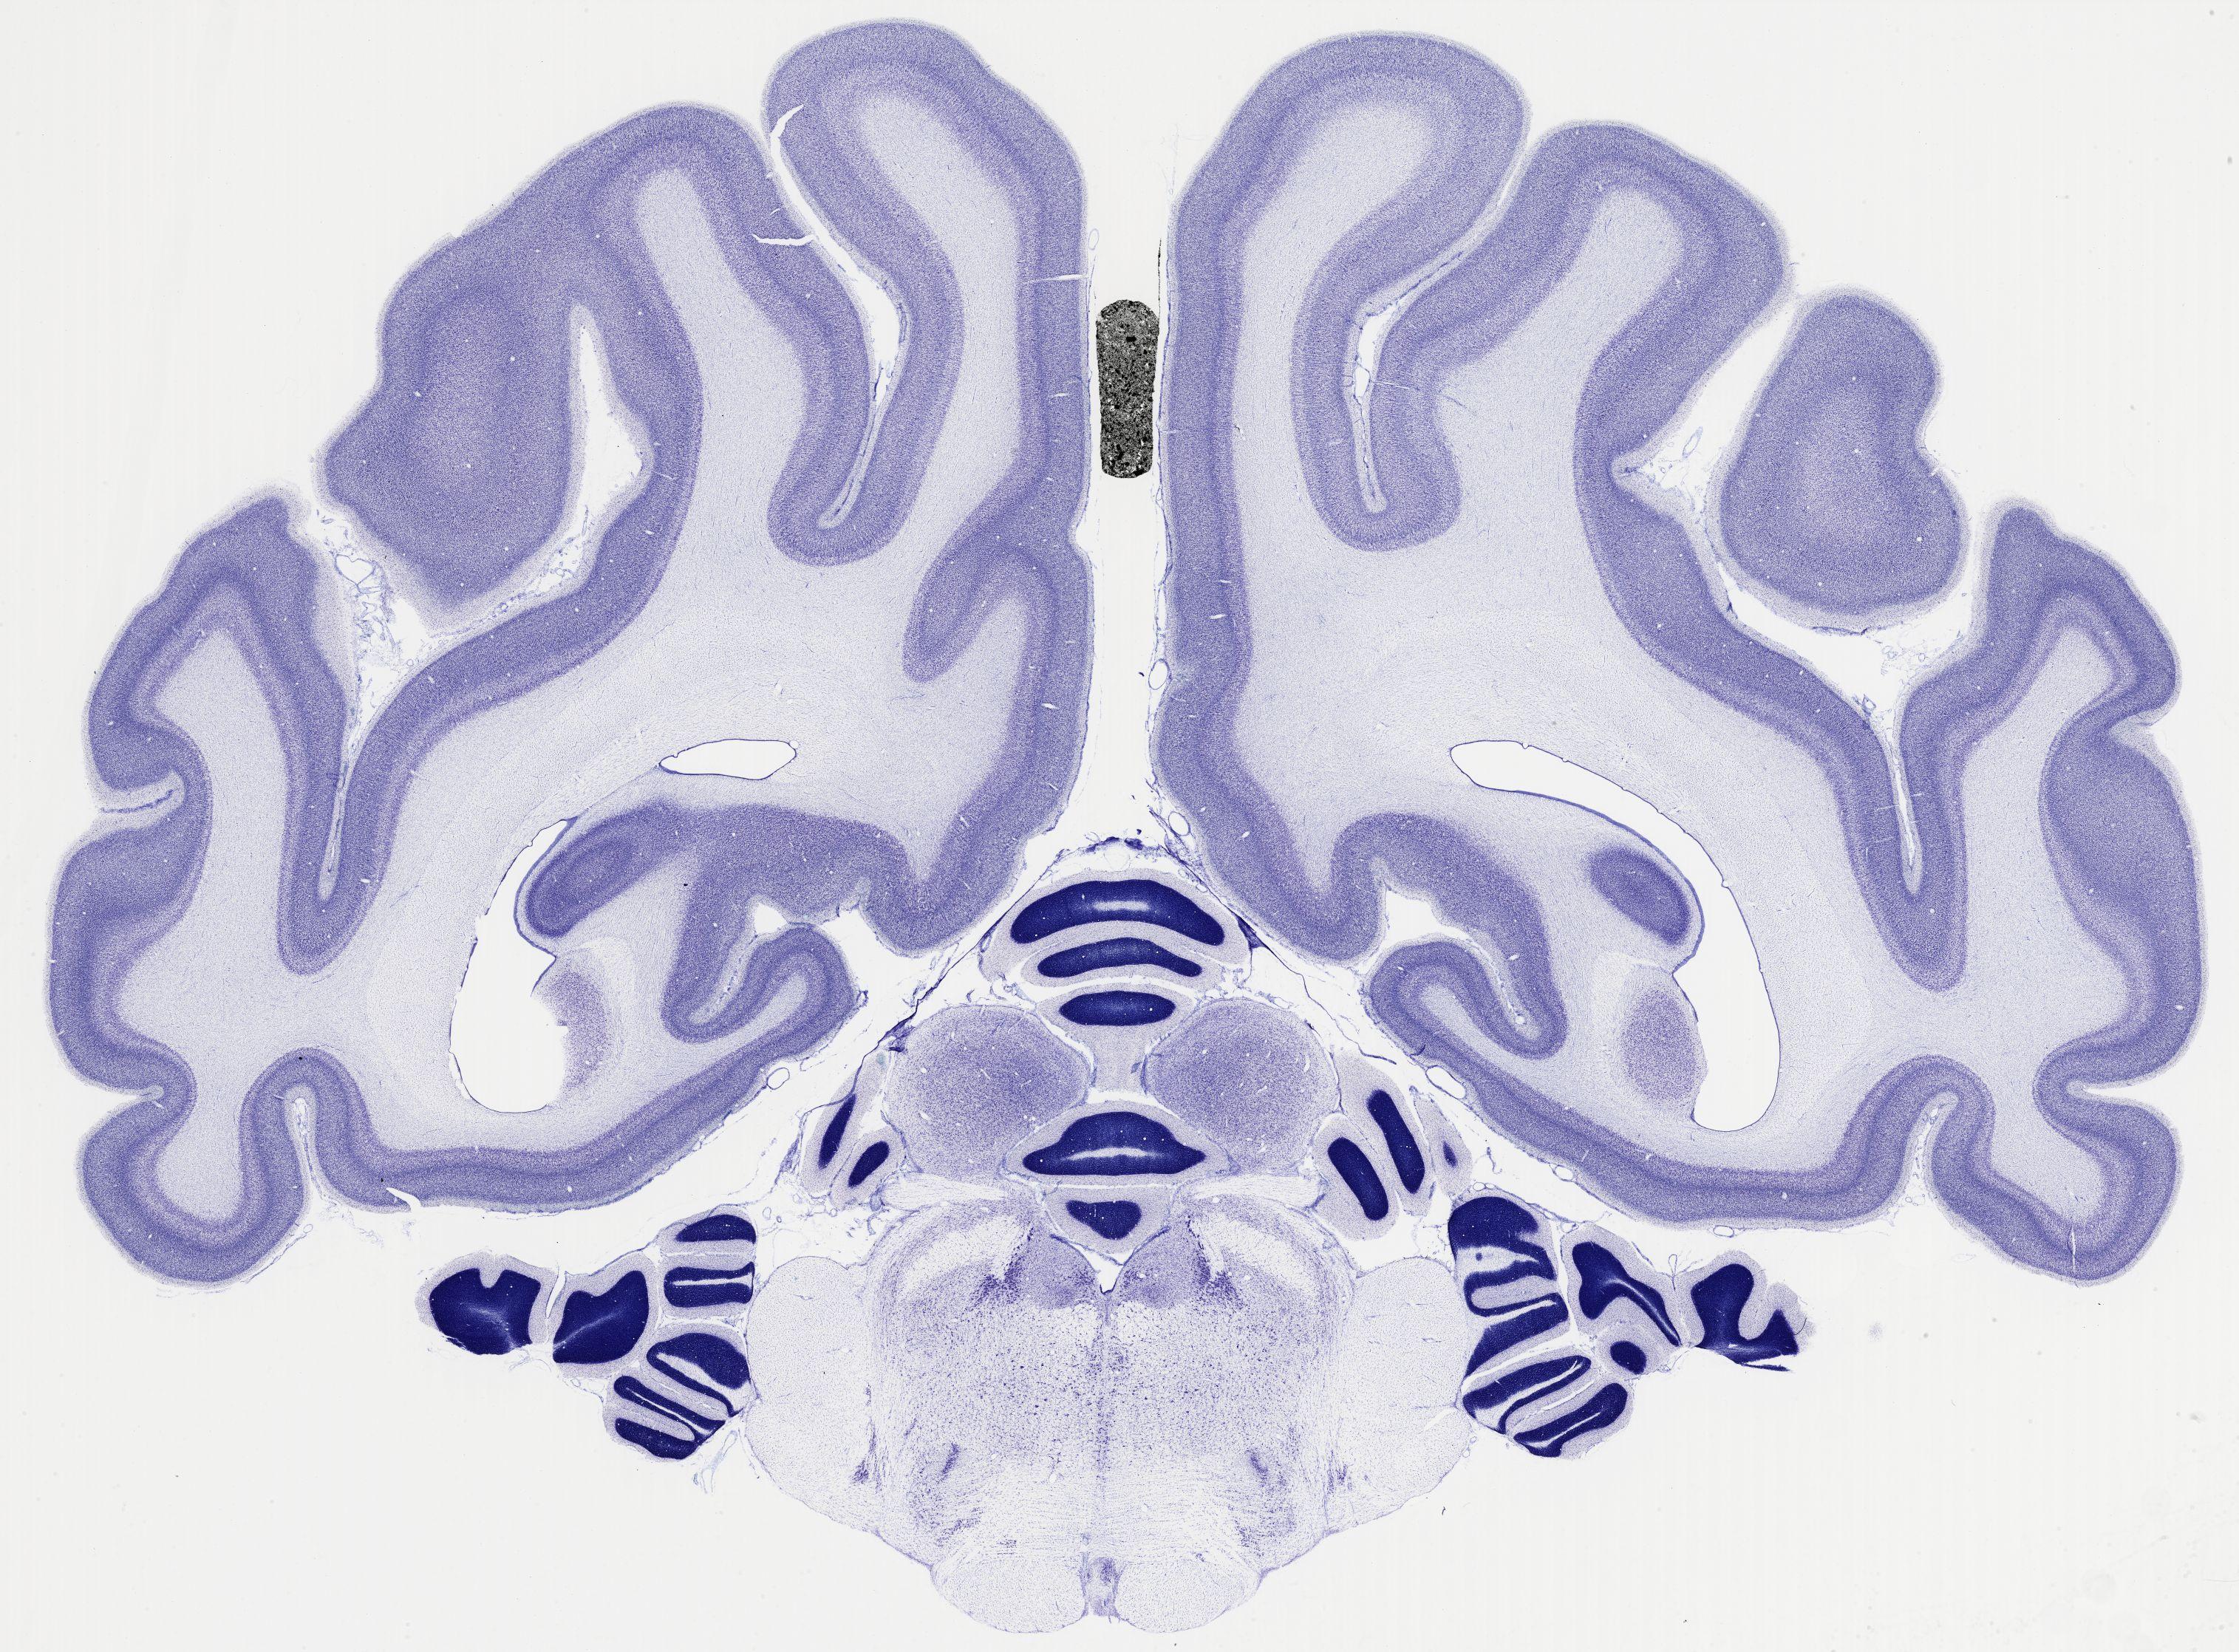

Datasets -> Chlorocebus Aethiops -> Nissl, coronal, histo, Whole-Brain, adult

[ Metadata ]   ·   Source: NeuroScience Associates

thumbnail

522